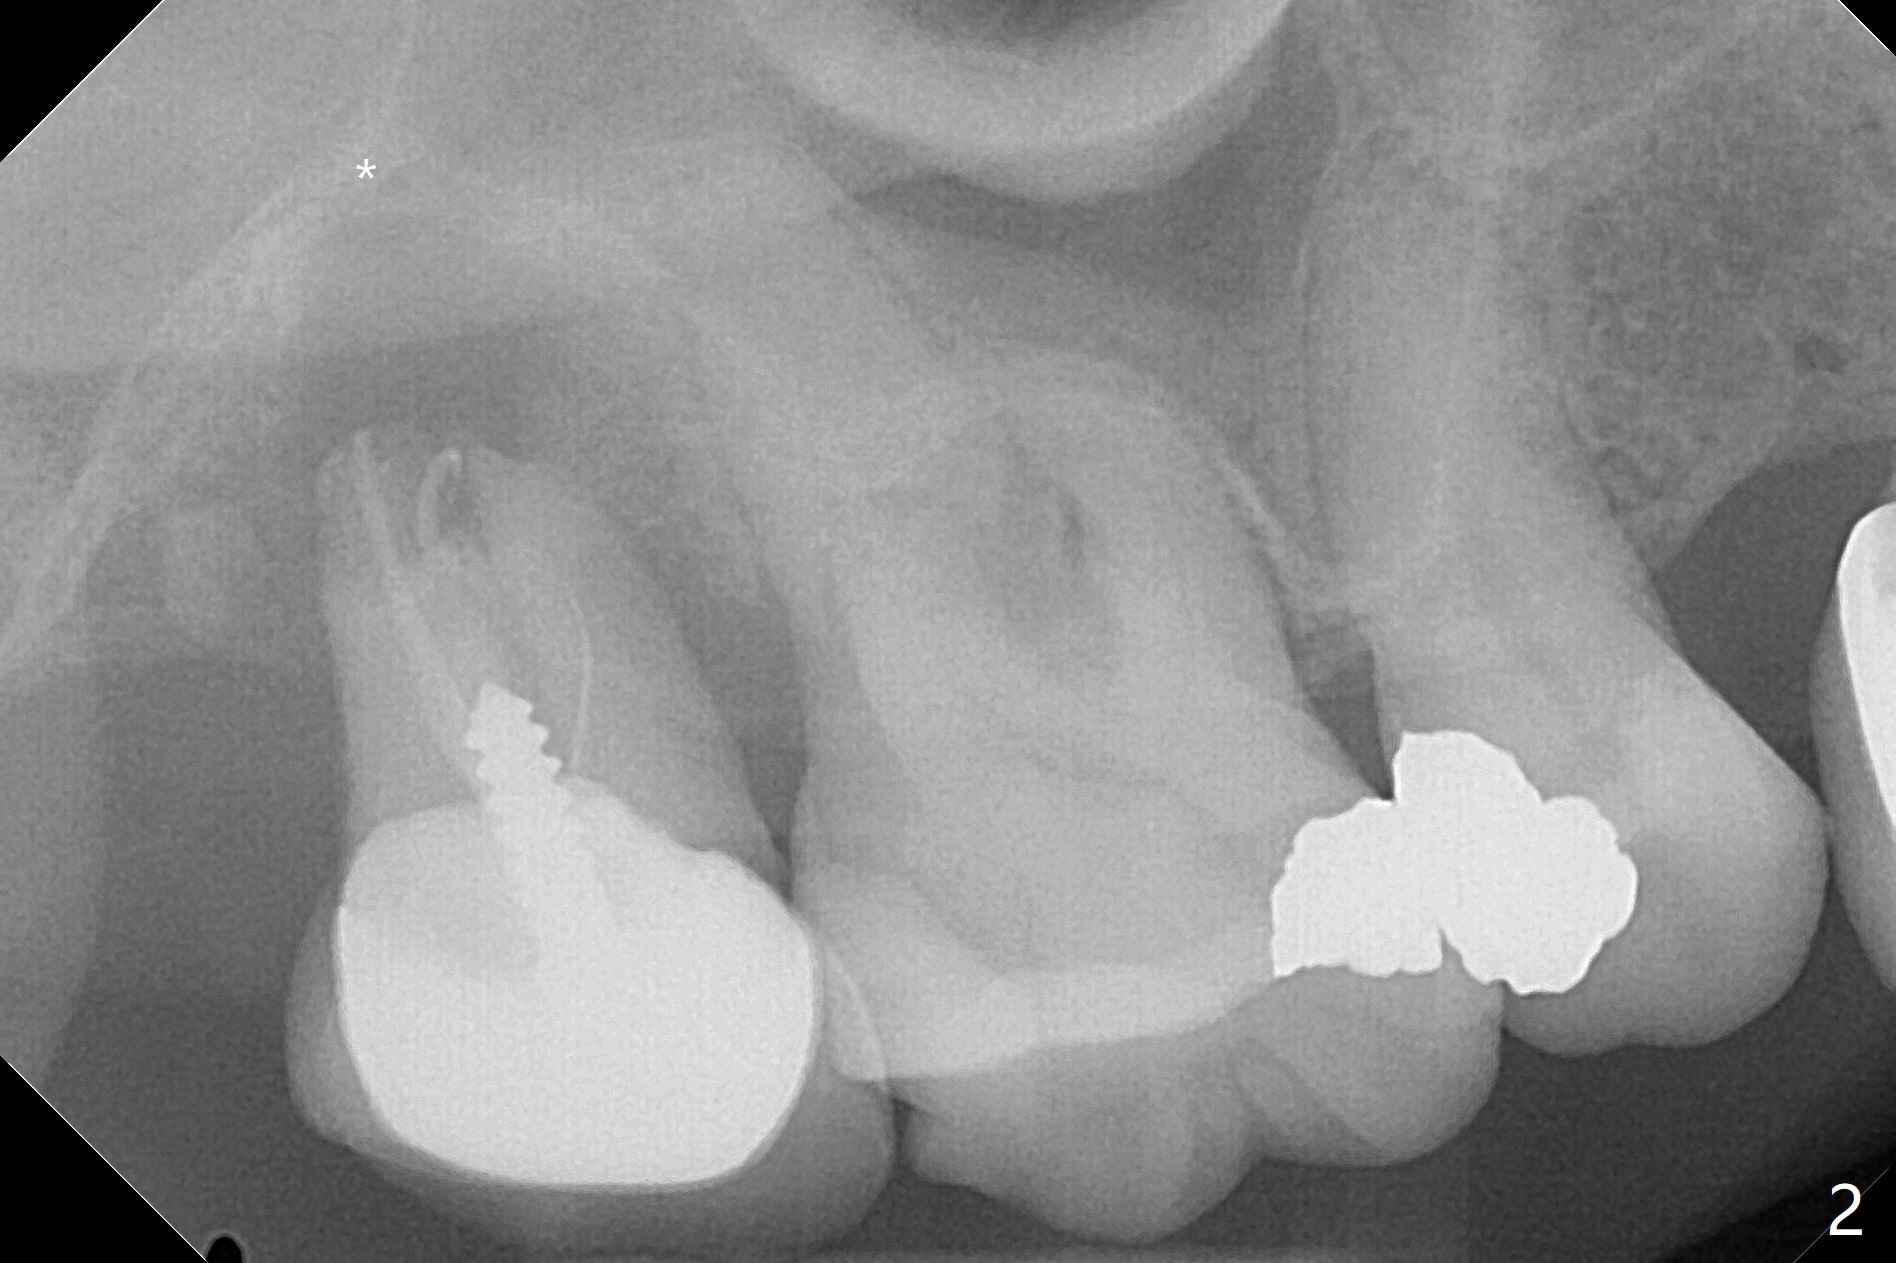

59岁女右上七骨质吸收严重(图一),上颌窦底板薄(图二:*),而窦膜厚(图三:*),应该容易提升,腭侧根吸收(图四:P),上颌窦底板穿孔(图五:*),拔牙后(图六:黑色),水提升(白箭头),放置PRF膜(黄色曲线)和粘性骨块(红色圆圈),最后完成位点保留(图七:大圆圈),放置另外一块PRF膜和6个月吸收膜,缝合,牙周或者树脂敷料。Return to No Deviation 19-21 位点保留后 导板与张口度 Xin Wei, DDS, PhD, MS 1st edition 09/09/2020, last revision 01/01/2021